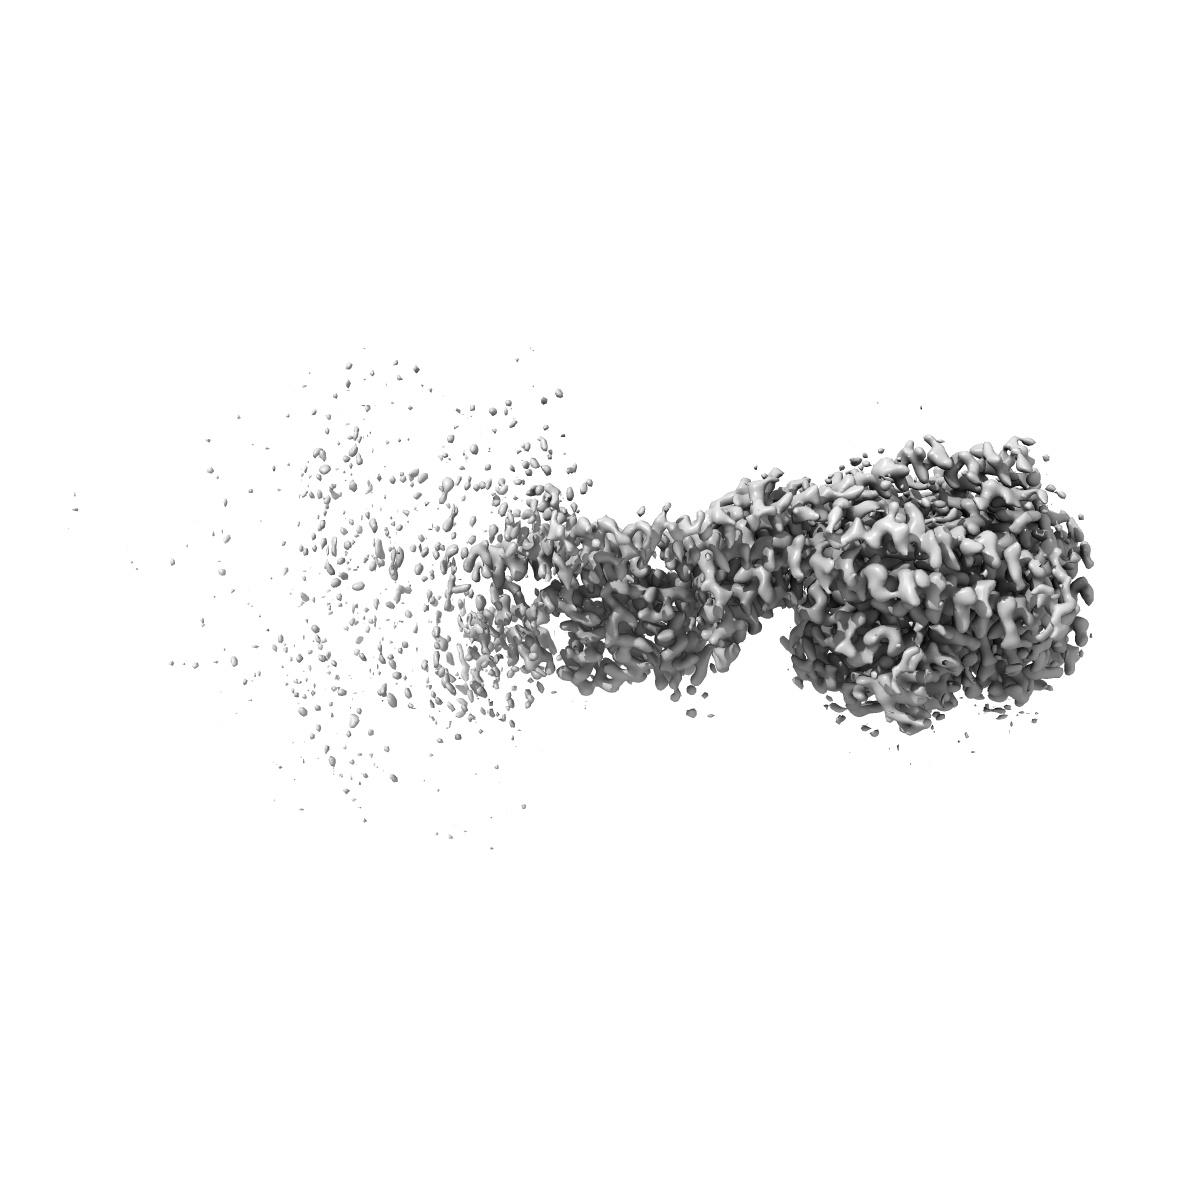

Cryo-EM structure of Mycobacterium tuberculosis ATP synthase Fo in complex with bedaquiline(BDQ)

Single-particle2.85 Å

Sample: Mycobacterium tuberculosis ATP synthase Fo with bedaquiline(BDQ)